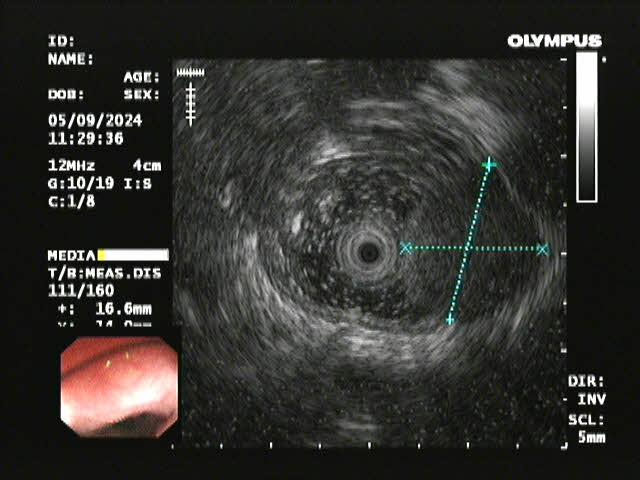

超声内镜

患者李某因胸骨后异物感20余天入院,在外院进行胃镜检查提示食管距门齿约26cm处见黏膜下肿瘤,在昆医大附二院超声胃镜提示该肿瘤呈低回声,局限于黏膜下层,固有肌层完整;胸部CT提示该肿瘤直径>2cm,位于食管中下段,增强扫描轻度强化,前与左主支气管相邻,后紧贴胸主动脉,手术过程中稍有不慎就可能发生大出血,危及患者生命,手术难度和风险可想而知。